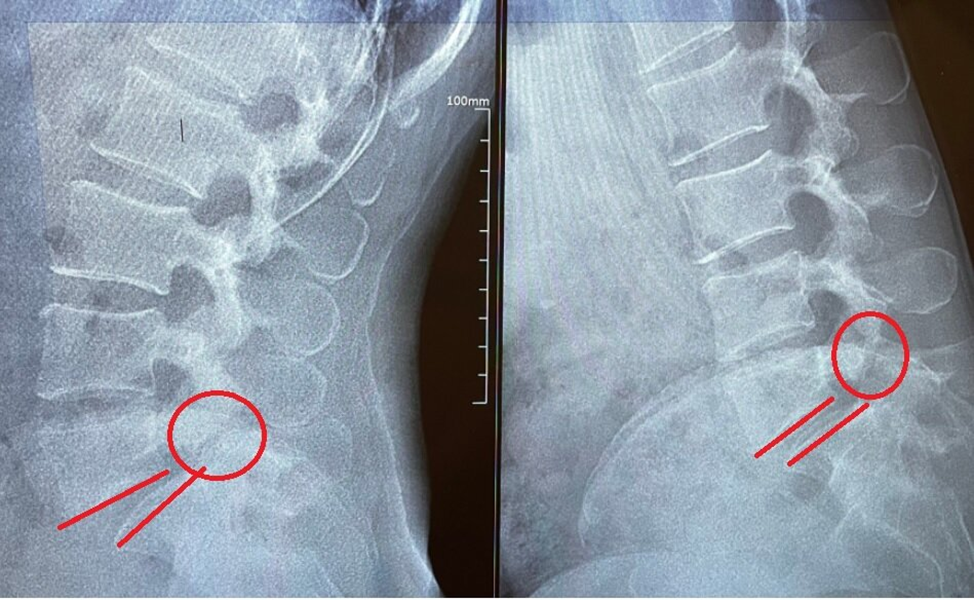

- И если вы взглянете на мои снимки. Мне ставят нестабильный листез 1 степени. Смещение 7-9 мм. Доктор:

- Так и есть. И листез (смещение) и спондилолиз (разрыв позвонка на две части переднюю и заднюю. Пациент:

Нестабильный листез на фоне спондилолиза.